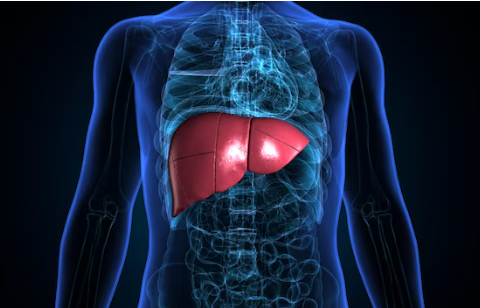

Quando o fígado não consegue mais se recuperar, doenças como cirrose, hepatites e esteatose avançada podem exigir o transplante como única solução

O fígado é um dos órgãos mais importantes do corpo humano, desempenhando várias funções essenciais. Ele ajuda na digestão, metaboliza nutrientes, filtra toxinas, armazena vitaminas e produz proteínas vitais. Além disso, ele tem uma característica única: a capacidade de se regenerar. Isso significa que, mesmo quando sofre danos por cirurgias, infecções ou exposição a substâncias tóxicas, o fígado pode se reconstruir e recuperar suas funções, desde que o agente agressor seja eliminado a tempo.

No entanto, essa habilidade tem limites, é o que alerta o Dr. Lucas Nacif, membro do Colégio Brasileiro de Cirurgia Digestiva (CBCD). “Quando os danos ao fígado são pontuais, ele consegue se recuperar bem. Mas se as agressões são frequentes e prolongadas, como acontece em casos de hepatites, gordura no fígado, uso excessivo de álcool ou certos medicamentos anabolizantes, o órgão começa a sofrer um desgaste contínuo, e nesses casos, em vez de se regenerar, o fígado começa a formar cicatrizes internas, um processo conhecido como fibrose” alerta.

O médico reforça que: “À medida que a fibrose avança, pode surgir a cirrose, que compromete a estrutura e reduz a regeneração do fígado. Com a agressão contínua, o órgão perde a capacidade de se recuperar e passa a falhar. No estágio avançado, o tecido saudável é substituído por cicatrizes que não exercem suas funções vitais, e a regeneração praticamente para, deixando o transplante como única alternativa.”